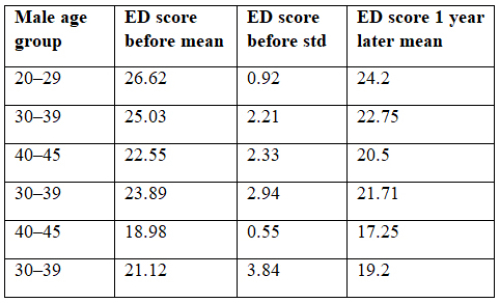

Yunus Çolakoğlu, Ali Emre Fakir, Ali Ayten, et al.

Penile prosthesis implantation (PPI) is a highly effective

treatment for men with erectile dysfunction (ED) who fail

first- and second-line therapies []. The modern inflatable

penile prosthesis (IPP) era began in 1973 when Brantley Scott

reported implanting silicone bodies, a reservoir, and a control

pump in five patients []. Early IPPs, while effective for organic

ED, had mechanical failure rates up to 50% within five years

[]. Prosthesis infection, a severe complication in andrological

surgery, increases morbidity and healthcare costs, exceeding

initial implant costs by over six times []. Infection rates range

from 2% for primary implantations to 18% for replacements [].

Despite high patient satisfaction with IPPs, issues

like discomfort, inadequate inflation, deformity, palpable

abnormalities, or painful intercourse may require revision

surgery []. Revision surgery effectively addresses infections,

mechanical failures, or patient dissatisfaction, with most

patients satisfied post-revision []. Most patients undergoing IPP

replacement report satisfaction and need no further intervention

[]. However, revision surgery carries higher risks of infection

and complications than primary surgery [], posing challenges

for patients, surgeons, and healthcare systems []. This study

evaluates the feasibility and safety of PPI revision surgery.

Savaş Özgür Ağlamış, Selver Kübra Akkaya, Ahmet Asfuroğlu

Two major earthquakes with moment magnitudes of 7.8 and

7.5 struck the southern and eastern Türkiye on 6 February 2023,

directly and indirectly affecting 15 million people and causing

more than 50000 lives []. The earthquakes were followed by at

least 11,000 aftershocks with moment magnitudes up to 6.7. The

earthquakes of 6 February 2023 were recorded as the earthquakes

with the highest number of casualties throughout the history of

the Republic of Turkey []. After the earthquake, survivors were

faced with a lack of food, thirst, cold weather conditions, health

problems, and shelter problems for a long time.

The most common problems faced after natural disasters

such as earthquakes are sexual disorders and fertility health

[]. The extent of contraceptive methods, sexual violence, and

the prevalence of sexually transmitted diseases are among the

main consequences of earthquakes for sexual and reproductive

health []. The present study aims to underline the need to

understand whether or not male and female earthquake survivors

were affected in terms of their sexual function and interest in

sexuality, the symptomatology, prevalence, and associated risk

factors of sexual dysfunctions after the initial shock effect of the

earthquake have subsided and the problem of temporary shelter

has been solved.